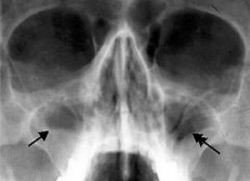

• ančių (Waters) radiogramą (3 pav.) – matomas žievinio kaulo netekimas, ančio gleivinės sustorėjimas, ančio užtemimas (2, 3, 6).

3 pav. Ančių (Waters) radiograma, kurioje stebima skysčio ir oro linija dešiniame antyje (11)

Kartais, kai yra pašalintas uždegimą sukėlęs dantis ir įtariama, kad žandinis antis susijungia su burnos ertme, radiologinis tyrimas atliekamas su gutaperčios kaiščiu alveolėje (3). Uždegimui esant odontogeninės kilmės, ligą sukėlusio danties vainike bus stebimas danties ėduonis ar užpildas arti pulpos kameros. Stebimi ir periodonto radiologiniai pakitimai – padidėjęs ir išplatėjęs periodonto plyšys su kaulo destrukcija (3). Kartais antyje gali būti randama plombinės medžiagos ar lūžusių endodontinių instrumentų (2–4, 6). Pašalinus OŽS sukėlį dantį, žandiniam ančiui jungiantis su burnos ertme, matoma šio danties alveolė, nepripildyta kaulo, ir nevientisas, suardytas, su defektu žandinio ančio apatinės sienos radiologinis vaizdas. Atliktos žandinio ančio radiogramos yra lyginamos – dešinė yra lyginama su kaire (2). Radiologiniuose vaizduose stebimas gleivinės paburkimas, kuris gali būti lokalus, dėl pūlingo uždegimo matoma vadinamoji skysčio linija (3 pav.), užtemęs sinusas (2–4, 9).